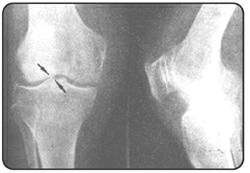

软骨分为透明软骨、纤维软骨和骨软骨,主要包括软骨细胞和基质,基质的理化特性受基质成分的影响。临床上中老年人常见的骨关节炎就是一种慢性软骨损伤所产生的疾病。骨关节炎多发生在膝、髋、腰椎、颈椎等部位,其中膝关节的发生率最高,因此我们重点介绍膝关节骨关节炎。膝关节骨关节炎多发生在50岁以后,女多于男。流行病学调查表明,55岁以上中老年人膝关节骨关节炎的发生率为44%~70%,换句话说即每两名中老年人中,就有一名一生中将患有膝关节骨关节炎。病人常主诉膝关节酸痛,先是上下楼梯时膝痛明显,下蹲时同时出现膝酸痛,继而发展到平地行走时单侧或双侧膝部酸痛。病人还主诉行走尤其上下楼后酸痛加剧,有时还会伴膝部肿大。X线检查可以发现疼痛的膝关节有赘生物,俗称“骨刺”,关节腔内积液,甚至发现膝关节间隙变狭窄。